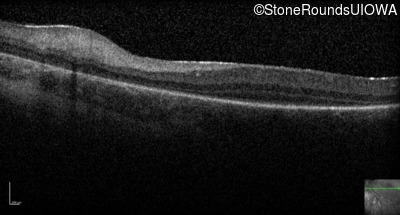

Optical Coherence Tomography - Right -

No Light Perception

Exemplar

Expanded OCT Stack

×